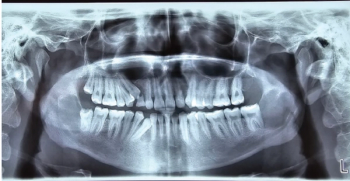

A case study by Sahith Kumar Shetty, BDS, MDS, et al reviews the need for a multidisciplinary approach to the treatment of patients with Gorlin-Goltz syndrome.